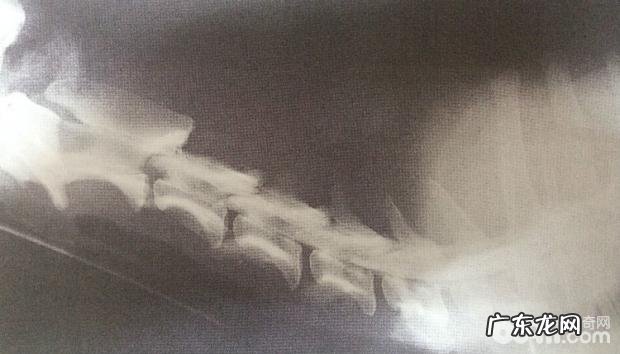

图4.3 B某患犬L5-6腰椎穿刺脊神经造影检查

由图4.3 B能够看得出,L3锥体减少 。在这里位置造影检查柱终断 。

确诊:依据照片,融合患犬平时主题活动,病历等,确诊出此患犬第三椎间盘外伤骨裂,脊神经遭受挤压 。